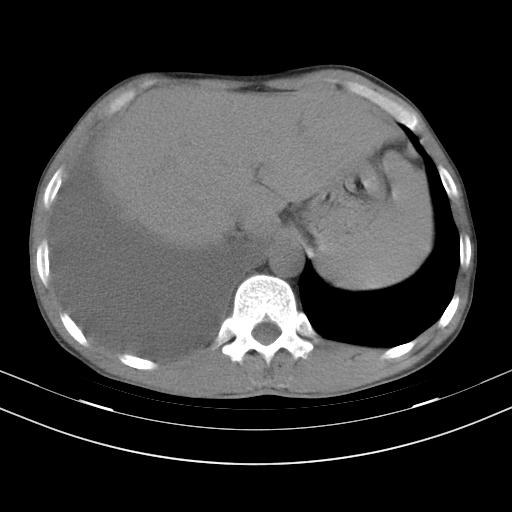

男性,44岁,结核病史多年。现胸闷气短,咳嗽,偶咳血。

右侧胸腔积液

右肺下叶不张

双肺多发结节影最分空洞形成考虑占位不除外结核

双肺陈旧性病变

1、右侧大量胸腔积液伴右肺压缩性膨胀不全,建议抽液治疗后复查 2、两肺继发性tb伴空洞形成。

1)两肺继发性肺结核伴空洞形成,左肺多发性结核球。2)右侧大量胸腔积液伴右肺部分膨胀不全。3)纵隔淋巴结肿大。